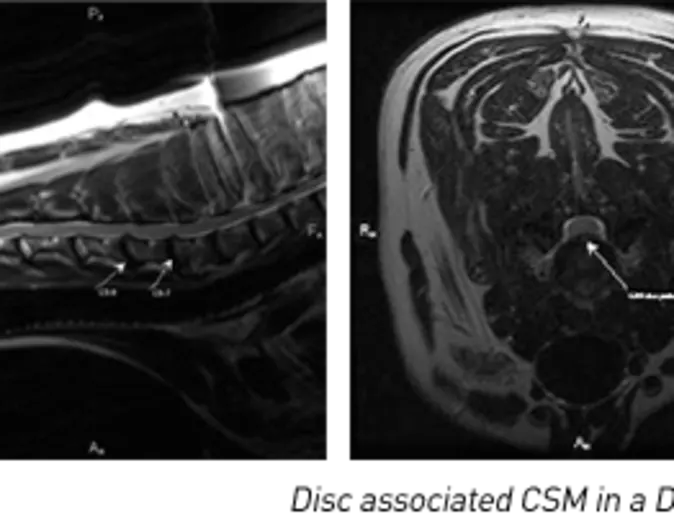

Cervical Spondylomyelopathy (CSM)

CSM is a disease that affects the cervical spine in large and giant breed dogs. The etiology is multifactorial and thought to represent a combination of genetic, nutritional, and degenerative causes.